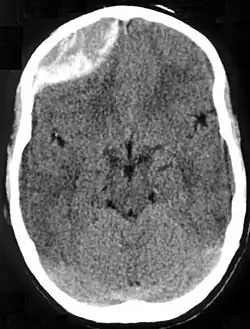

| Epidural hematoma as seen on a CT scan with overlying skull fracture. Note the biconvex shaped collection of blood. There is also bruising with bleeding on the opposite side of the brain. | |

Epidural hematomas usually appear convex in shape because their expansion stops at the skull's sutures, where the dura mater is tightly attached to the skull. Thus, they expand inward toward the brain rather than along the inside of the skull, as occurs in subdural hematomas. Most people also have a skull fracture.[3]

Epidural hematomas may occur in combination with subdural hematomas, or either may occur alone.[10] CT scans reveal subdural or epidural hematomas in 20% of unconscious people.[15] In the hallmark of epidural hematoma, people may regain consciousness and appear completely normal during what is called a lucid interval, only to descend suddenly and rapidly into unconsciousness later. This lucid interval, which depends on the extent of the injury, is a key to diagnosing an epidural hematoma.[3]